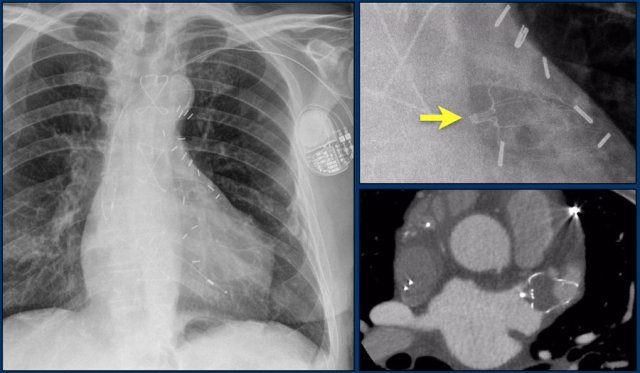

First study the images.

Then continue reading.

The findings are:

• Two epicardial leads connected to pacemaker

• ICD

• two leads to right ventricular apex

• one lead contains two shock coils

• tricuspid valve (arrows)

• mitral valve